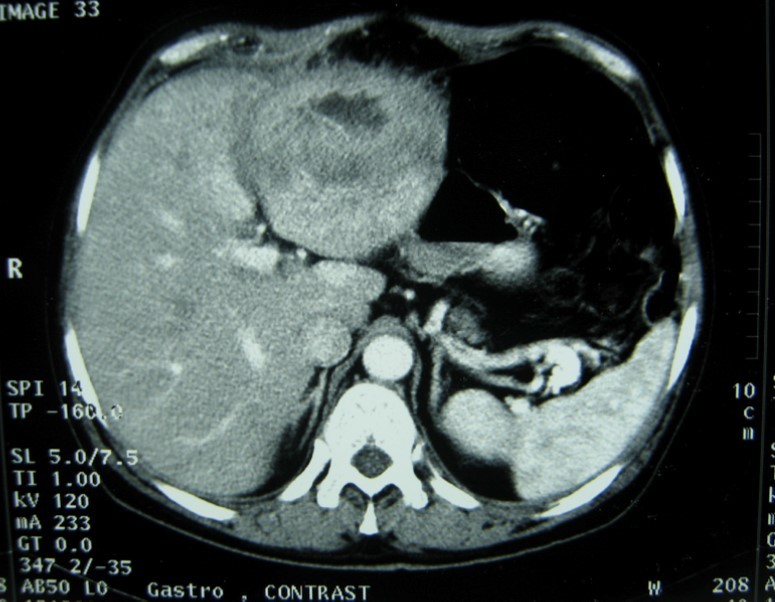

Laboratory analysis showed hemoglobin, 10.9 g/dL; white blood cell count, 9,800 cells/mm3, serum albumin, serum total bilirubin, alanine aminotransferase, aspartate aminotransferase, prothrombin time, hepatitis B surface antigen, and antibodies to hepatitis C, serum alpha-fetoprotein (AFP), carcinoembryonic antigen and carbohydrate antigen 19-9 (CA 19-9) were within normal range. Blood cultures were negative. Chest x-ray was normal. Ultrasound of abdomen showed a 10 cm hypoechogenic lesion in left liver (Figure 1). An abdominal CT showed a well-defined heterogeneous mass situated in his left hepatic lobe measuring 10 cm × 7 cm (Figure 2, Figure 3). The lesion featured central necrosis, a hyper-dense rim and a mild enrichment from the arterial phase in the CT, The diagnosis of primary hepatic tumor was suspected. An ultrasonography-guided needle biopsy of the liver was scheduled in order to rule out malignancy and to have a complete diagnosis. Cytology demonstrated a tuberculosis granuloma, acid-fast bacilli culture was positive (Figure 4). Anti-tuberculous therapy including isoniazid, rifampin, ethambutol, and pyrazinamide were prescribed. The patient completed the 6-month course of medication with success. The patient’s appetite and body weight were restored to previous levels. One year after the completion of treatment, the patient remained completely asymptomatic with disease free.

Figure 3.Abdominal computed tomography with intravenous contrast showing the lesion with ring enhancement.

CT findings of tuberculosis abscesses can show low-density focal lesions with or without ring enhancement on contrast administration. These have also been seen in necrotic tumor such as hepatocellular, inflammatory disease and metastatic carcinoma 12.